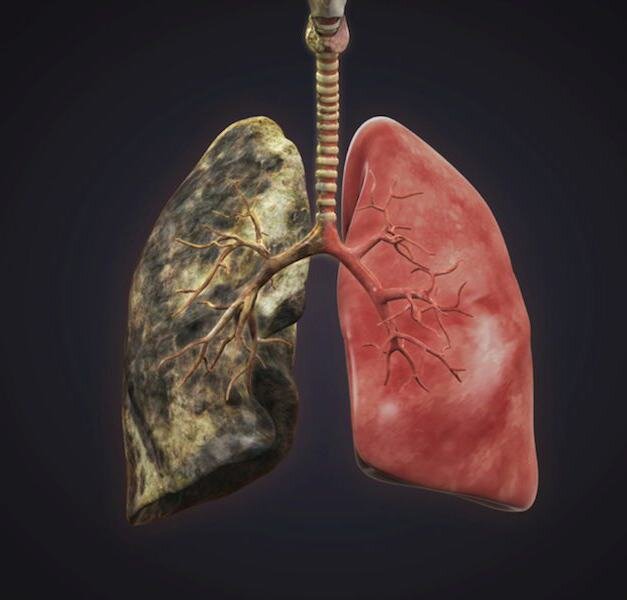

Часто на просторах всемирной паутины можно встретить картинки, показывающие вид легких некурящего и курящего человека. У некурящего органы розового цвета, а у курящего — черного. На пачках с табачной продукцией можно также увидеть неприятные картинки, на которых изображены якобы легкие того, кто много курил. То, что выдают за легкие курильщика, черные и ссохшиеся, будто пролежали в земле несколько лет. Но так ли это на самом деле?

Правда ли, что легкие курильщика сильно отличаются от легких некурящего человека? На самом деле, курение, хоть и увеличивает риск развития заболеваний легких, но далеко не всегда так изменяет внешний вид самих органов. На самом деле на картинках с «легкими курильщика» показаны органы с запущенной стадией серьезных легочных заболеваний, при которых начинается некроз тканей. Но курение — далеко не единственная, а лишь одна из многих возможных, причин развития этих состояний. Сказать, какие легкие принадлежат некурящему человеку, а какие курильщику не всегда берутся даже патологоанатомы. У курящих людей в равной степени могут быть как пораженные заболеванием, так и совершенно нормальные на вид органы.